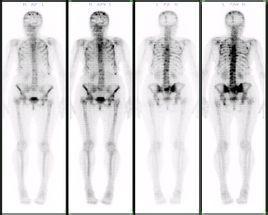

骨扫描:如果CT或MRI检查怀疑骨转移时,可以考虑行全身骨扫描检查,明确是否有骨转移

。